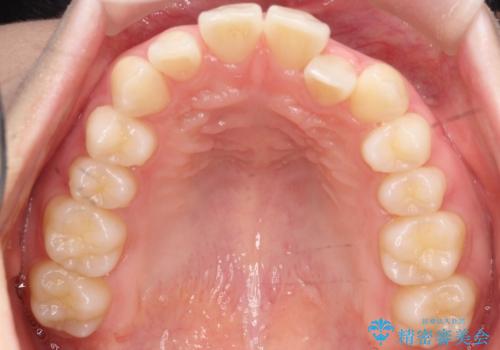

- 左上2の反対咬合(交叉咬合)をインビザラインを用いて治療しました。反対咬合は、歯列の不正咬合の一つであり、上の歯が下の歯よりも内側に位置する状態です。反対咬合は咀嚼や発音に影響を与えることがあります。

左上2の反対咬合をインビザラインで治療する際に、IPR(Interproximal Reduction)を行いました。 IPRとは、隣接する歯の間のエナメル質をわずかに削る手法で、歯の幅を減少させることによって歯列を整える技術です。